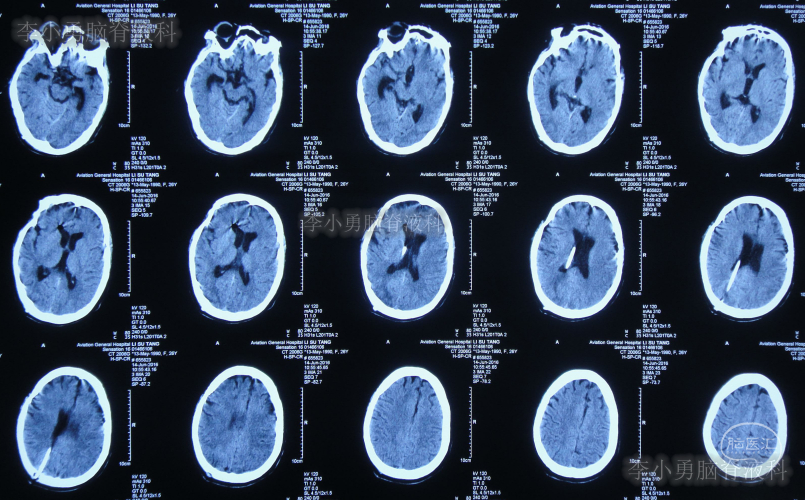

家属为进一步明确病因即2016年4月4日,第2次就诊并住入第二家的上海市静安区的某三甲医院,复查头颅影像后(图-3、图-4),给予按癫痫进行治疗。

图-3:2016年4月4日头颅CT

图-4:2016年4月4日头颅影像